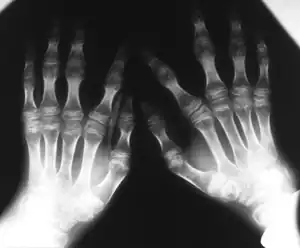

| Kniest dysplasia- Hands demonstrate flattening of metacarpal epiphyses, carpus has a disorganized aspect | |

The images taken will help to identify any bone anomalies. Two key features to look for in a patient with Kniest dysplasia is the presence of dumb-bell shaped femur bones and coronal clefts in the vertebrae. Other features to look for include:

- Abnormal growth of epiphyses, metaphyses, and diaphysis

- Short tubular bones